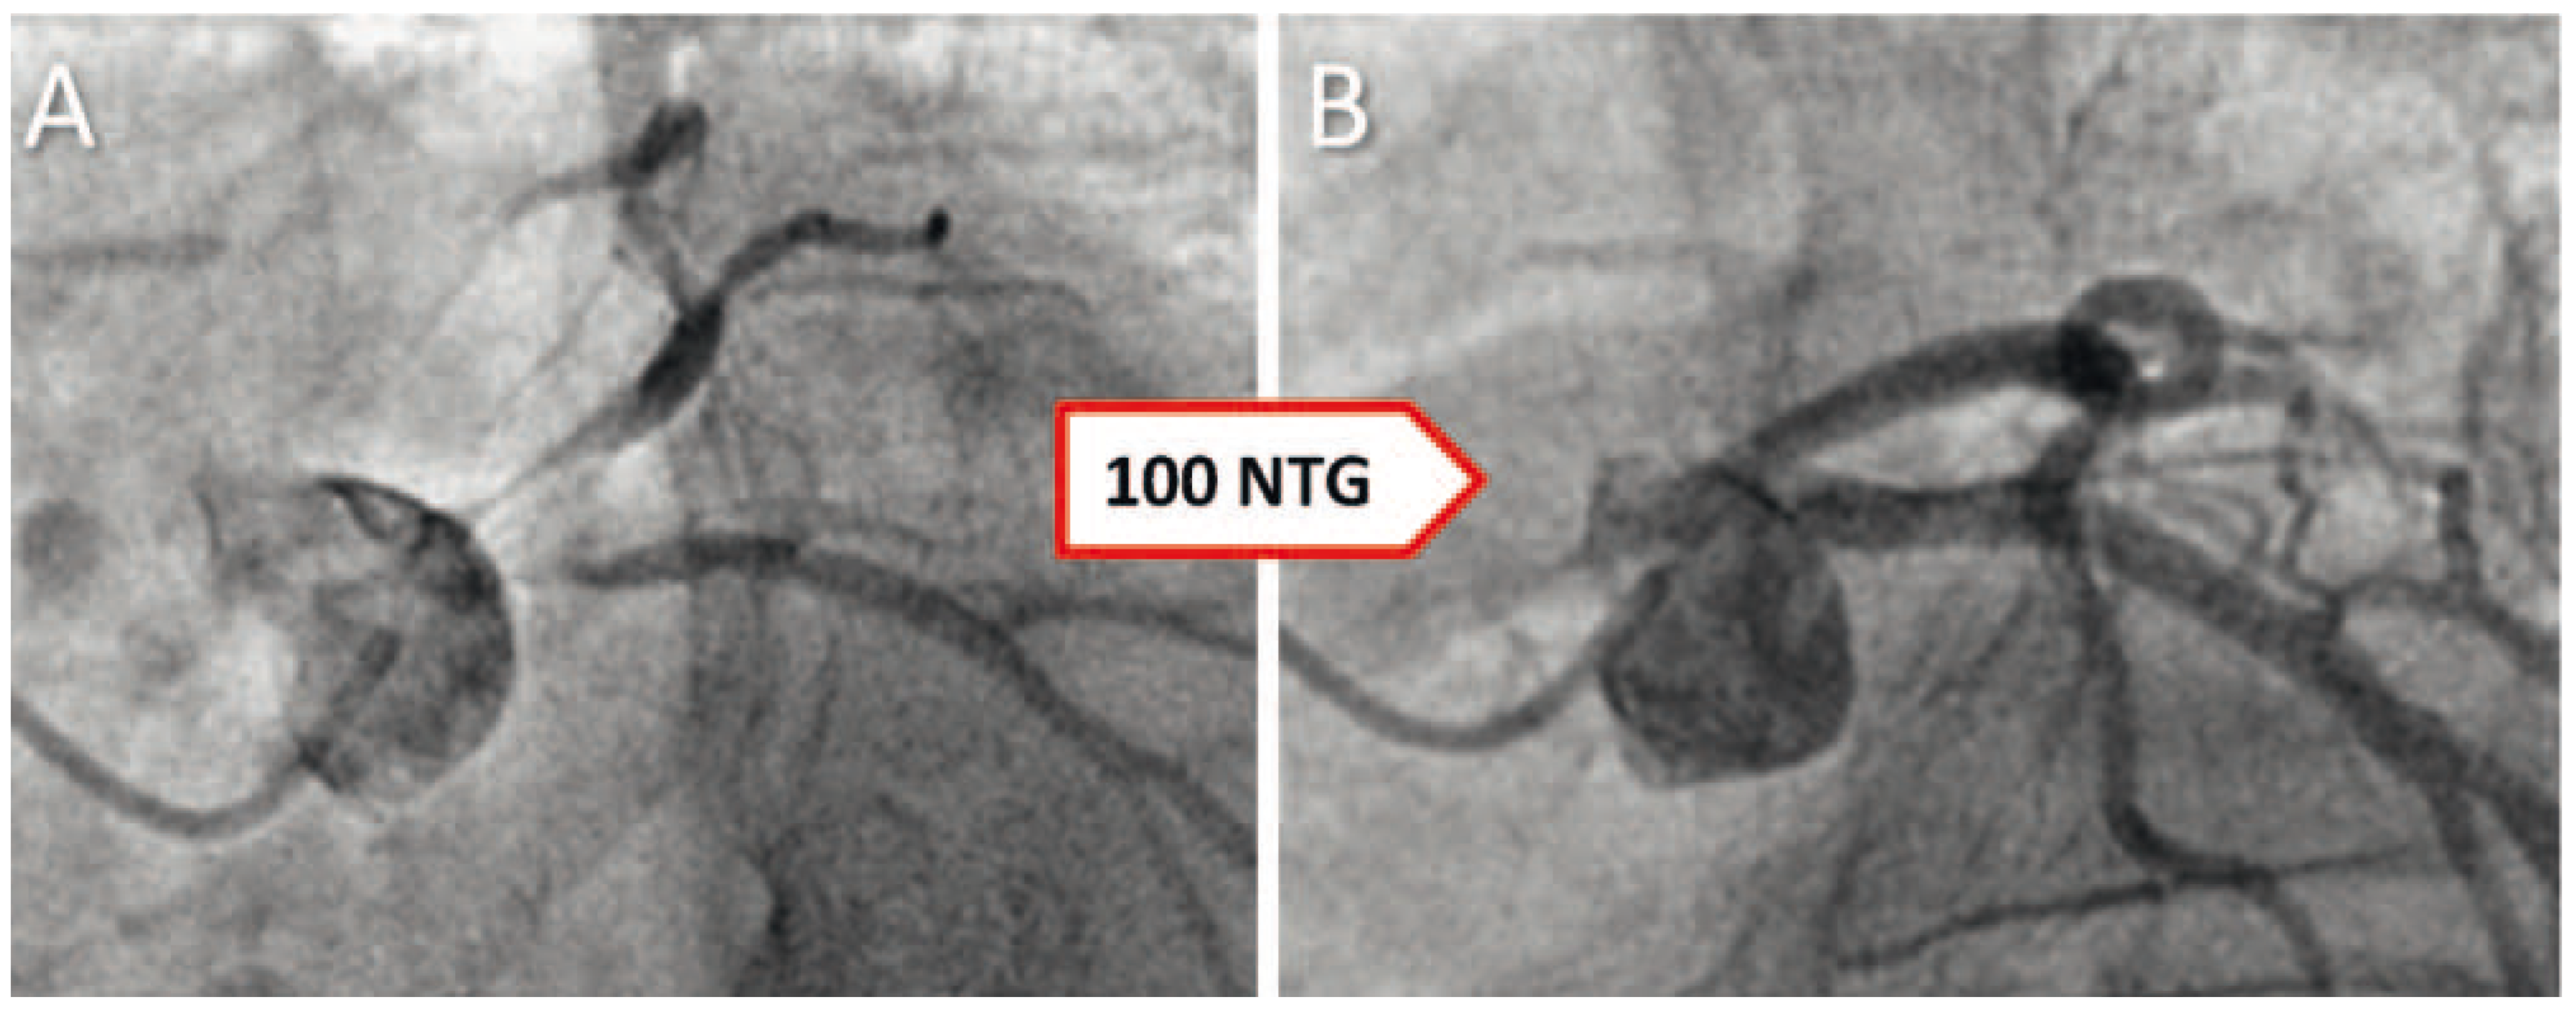

Case report

Does hyperthyroidism induce coronary vasospasms?